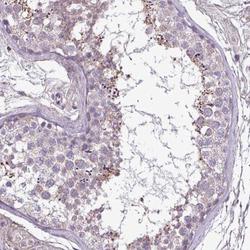

- Immunohistochemistry: FAM183A Antibody [NBP2-33550] - Immunohistochemical staining of human testis shows cytoplasmic positivity in cells in seminiferous ducts.